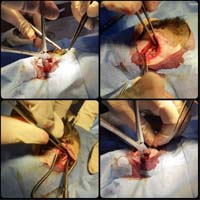

Bodrum Yalıkavak'taki kliniğimizde gerçekleştirdiğimiz yumuşak doku cerrahi uygulamaları:

Aslında bu cerrahi alan oldukça geniş bir alanı kapsamaktadır. Fakat siz yırtılan ya da kesilen deriye uygulanan cerrahi işlemler olarak düşünebilirsiniz. Daha detaylı anlatmak gerekirse; Örneğin; Erkek bir kedinin üriner taşlarından dolayı sondayla denenmesine rağmen açılmayan idrar kanalına yapılan dişileştirme operasyonu (perineal üretrostomi) da bir yumuşak doku cerrahisi operasyonudur.